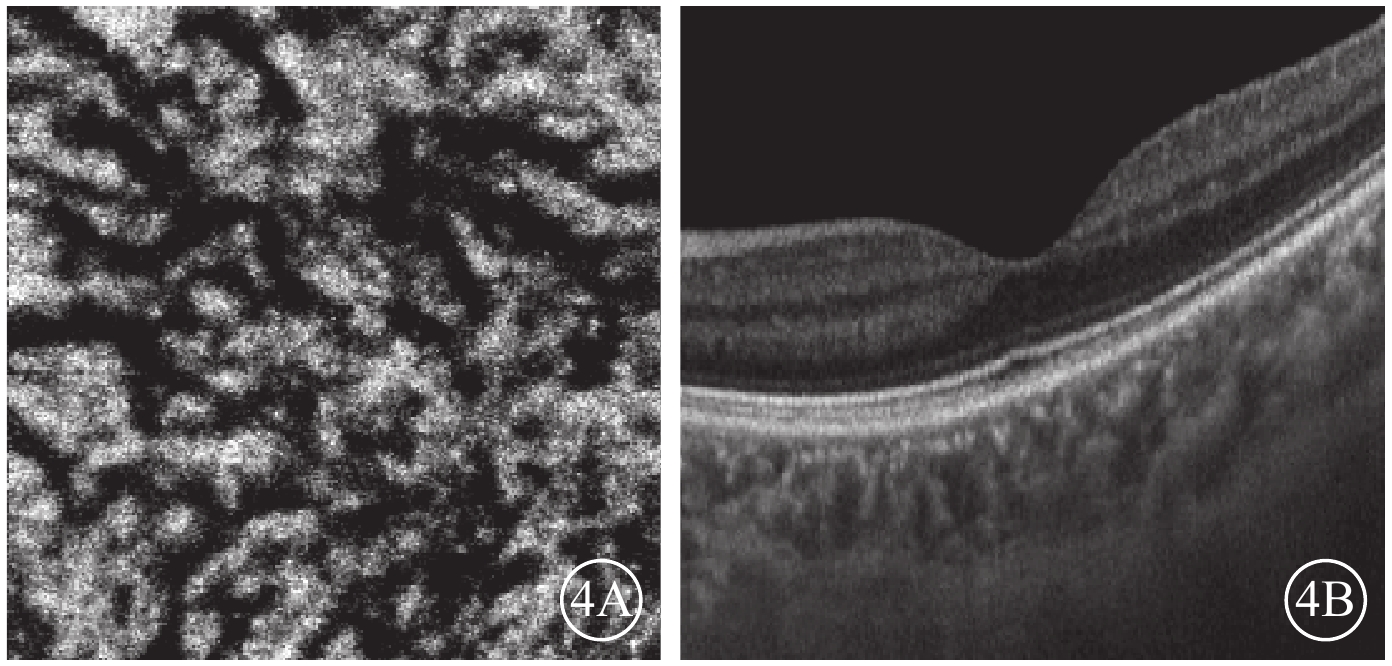

Bruch膜下1/2脈絡膜厚度層面,SS-OCTA圖像呈現與平面(en-face)OCT所示脈絡膜大血管分布較為一致的黑色血流信號,經二值化處理后所得的黑白圖像能反映脈絡膜大血管層的高速血流分布(圖2)。ECS組受檢眼脈絡膜SS-OCT和脈絡膜大血管層SS-OCTA表現為個別脈絡膜大血管極度擴張、高速血流匯聚和脈絡膜大血管普遍擴張、高速血流彌漫分布兩種類型。13只眼中,個別脈絡膜大血管極度擴張、高速血流匯聚6只眼;脈絡膜大血管普遍擴張、高速血流彌漫分布7只眼(圖3),其中1只眼為漿液性脈絡膜視網膜病變。對照組受檢眼脈絡膜SS-OCT無明顯大血管擴張征象,脈絡膜大血管層SS-OCTA圖像顯示高速血流分散而細小(圖4)。ECS組、對照組受檢眼脈絡膜大血管層FBFD分別為(76.35±14.46)%、(63.57±13.42)%;兩組受檢眼脈絡膜大血管層FBFD比較,差異有統計學意義(t=2.775,P=0.01)。

圖4

對照組脈絡膜大血管層en-face SS-OCTA和B掃描圖。4A. en-face SS-OCTA,高速血流分散稀少;4B. B掃描圖,脈絡膜大血管無明顯擴張

圖4

對照組脈絡膜大血管層en-face SS-OCTA和B掃描圖。4A. en-face SS-OCTA,高速血流分散稀少;4B. B掃描圖,脈絡膜大血管無明顯擴張

Bruch膜下1/2脈絡膜厚度層面,SS-OCTA圖像呈現與平面(en-face)OCT所示脈絡膜大血管分布較為一致的黑色血流信號,經二值化處理后所得的黑白圖像能反映脈絡膜大血管層的高速血流分布(圖2)。ECS組受檢眼脈絡膜SS-OCT和脈絡膜大血管層SS-OCTA表現為個別脈絡膜大血管極度擴張、高速血流匯聚和脈絡膜大血管普遍擴張、高速血流彌漫分布兩種類型。13只眼中,個別脈絡膜大血管極度擴張、高速血流匯聚6只眼;脈絡膜大血管普遍擴張、高速血流彌漫分布7只眼(圖3),其中1只眼為漿液性脈絡膜視網膜病變。對照組受檢眼脈絡膜SS-OCT無明顯大血管擴張征象,脈絡膜大血管層SS-OCTA圖像顯示高速血流分散而細小(圖4)。ECS組、對照組受檢眼脈絡膜大血管層FBFD分別為(76.35±14.46)%、(63.57±13.42)%;兩組受檢眼脈絡膜大血管層FBFD比較,差異有統計學意義(t=2.775,P=0.01)。

圖4

對照組脈絡膜大血管層en-face SS-OCTA和B掃描圖。4A. en-face SS-OCTA,高速血流分散稀少;4B. B掃描圖,脈絡膜大血管無明顯擴張

圖4

對照組脈絡膜大血管層en-face SS-OCTA和B掃描圖。4A. en-face SS-OCTA,高速血流分散稀少;4B. B掃描圖,脈絡膜大血管無明顯擴張